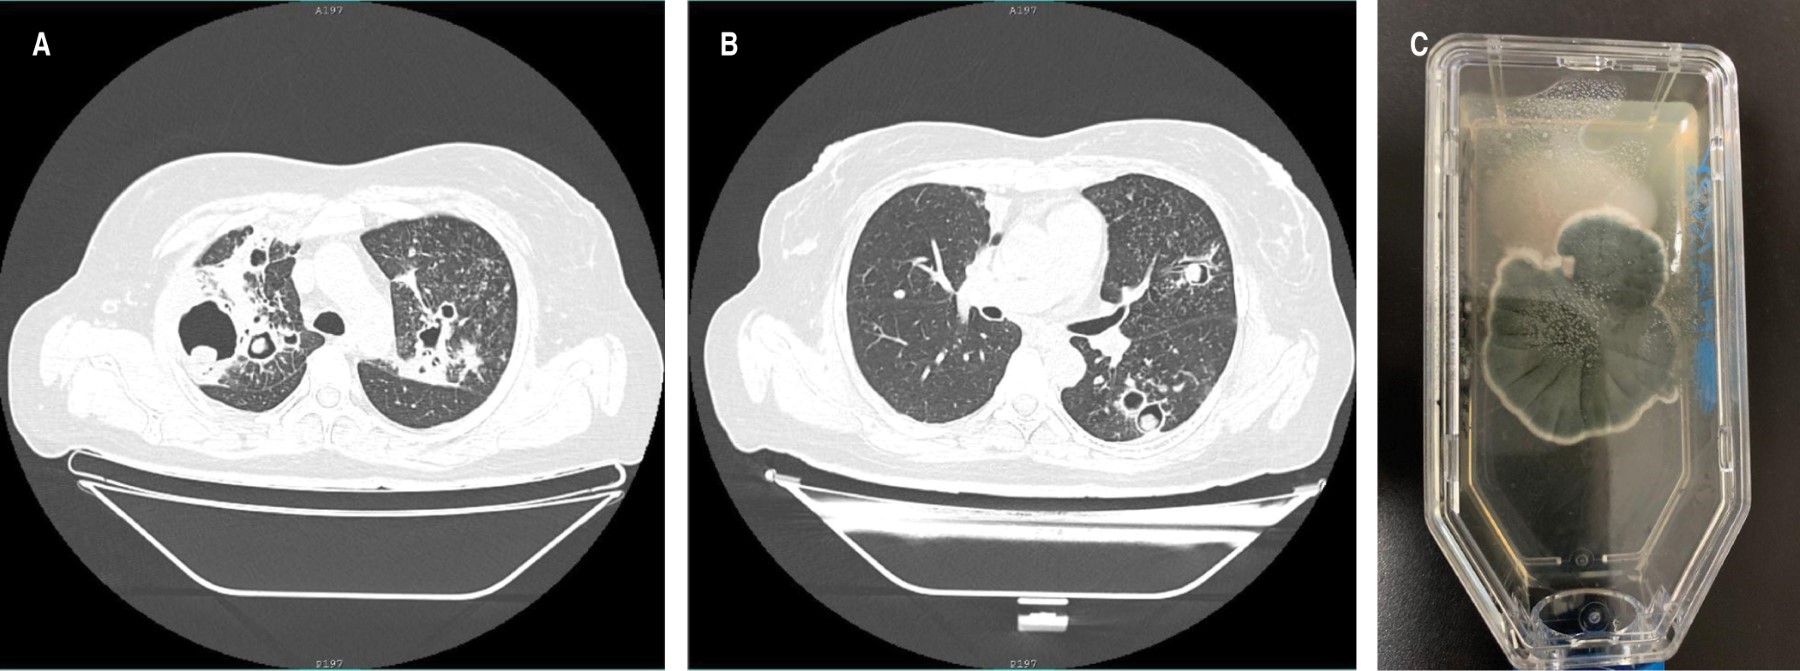

The chest radiograph showed multiple bilateral thin-walled cavities, with an intracavitary mass in several of them. Chest computed tomography (Figure 1A and 1B) confirmed the findings and allowed the identification of a greater number of cavities with an intracavitary mass.

Sputum fungal culture showed the simultaneous isolation of Coccidioides spp. and Aspergillus spp. (Figure 1C). The hospital unit does not have access to serology tests for these mycoses. She was started with itraconazole 300 mg every 12 hours, showing clinical improvement after a month of treatment.